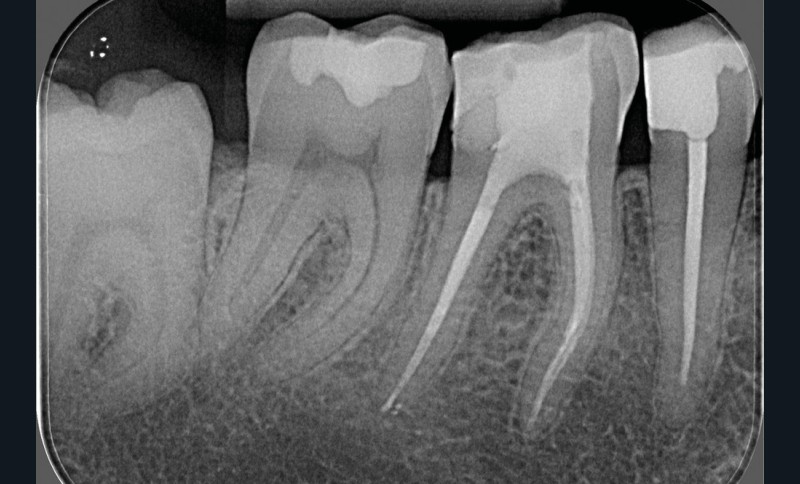

La préparation mécanique est principalement réalisée à l’aide d’instruments NiTi utilisés en rotation continue ou en réciprocité selon une approche corono-apicale. La mise en forme est ainsi plus rapide et respecte mieux le trajet canalaire initial qu’avec une instrumentation manuelle. Le diamètre apical et la conicité de la préparation canalaire font toujours débat. Ils dépendent de l’anatomie initiale et doivent permettre une irrigation efficace sans fragiliser la dent. Ainsi, un diamètre apical de 30 et une conicité de 6 % sont souvent proposés comme objectif minimal à atteindre [3] (fig. 1).

L’irrigation à l’hypochlorite de sodium (NaOCl) est utilisée depuis de nombreuses années en raison de son excellente efficacité contre le microbiote intracanalaire, tant à l’état planctonique que sous forme de biofilm [4, 5]. Le NaOCl, par son action protéolytique, a aussi la capacité de dissoudre les tissus organiques [6]. Il peut donc éliminer les débris pulpaires et le microbiote ayant échappé à la préparation mécanique au niveau de certaines portions des canaux principaux, des canaux accessoires et latéraux, des isthmes et autres delta apicaux. Ces zones sont surtout atteintes, nettoyées et désinfectées par l’irrigation. In vitro, l’action antiseptique, la capacité de dissolution des tissus organiques et la toxicité du NaOCl sont directement proportionnelles…